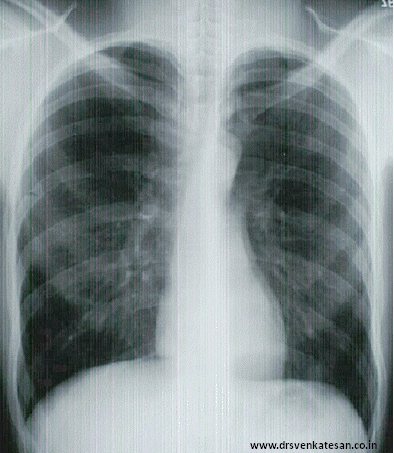

Have you ever wondered a given chest x-ray is taken in systole or diastole ?  We should . . .  isn’t ?  Statistically chances of a  X ray to  fall in  diastole is 10-20 % more than systole as the later phase is longer . The peculiarity of cardiac anatomy is that ,  the  profile of the heart alters so little between systole and diastole  .Still the blood is pumped  efficiently into both pulmonary and systemic circulation . The left ventricle shortens by 35%  and ejects 65 % of blood . Similarly RV shortens but with  lesser quantum.

ct ratio in systole and diastole influnce of cardiac cycle on ct ratio

In spite both ventricles contracting during systole the radiological transverse cardiac diameter is relatively undisturbed !